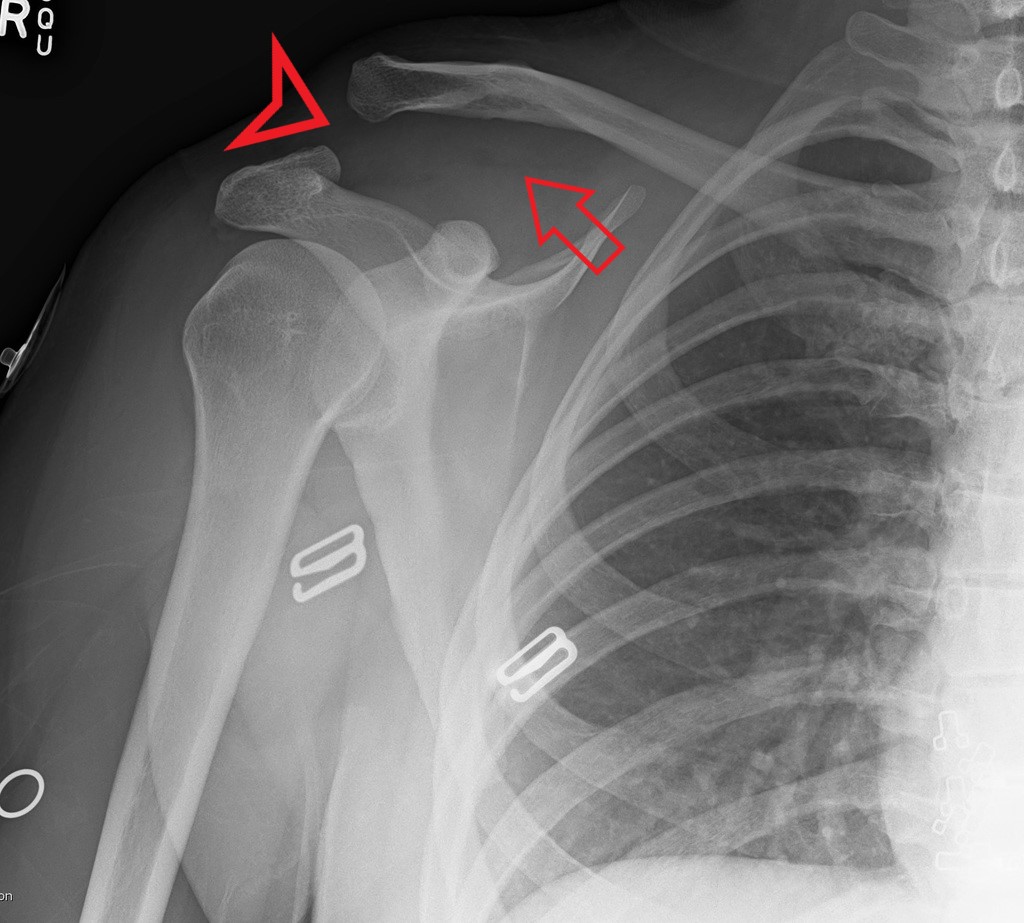

AC Joint Separation (red triangle) and widened coracoclavicular space Ac Joint Widening Treatment Learn about the causes, symptoms, and treatment of ac joint injuries, which occur when the shoulder blade and collar bone are separated or sprained. Find out the types of ac joint. Most have emphasized aspects of. Ac joint pain is a common problem that affects the tip of the shoulder blade (acromion) and the collarbone (clavicle). Multiple papers have described. Ac Joint Widening Treatment.

Imaging of the Acromioclavicular Joint Anatomy, Function, Pathologic